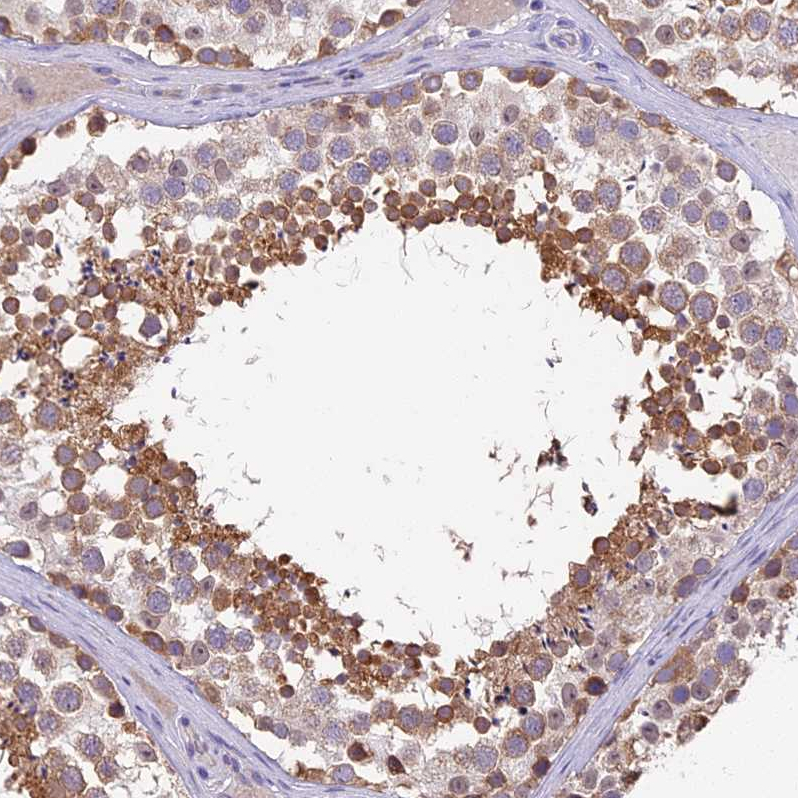

Immunohistochemistry analysis in human cerebral cortex and skeletal muscle tissues using HPA042394 antibody. Corresponding BSCL2 RNA-seq data are presented for the same tissues.